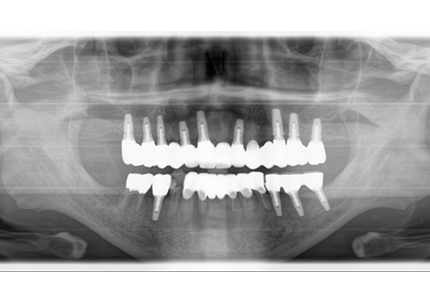

18.インプラント埋入後 パノラマレントゲン

患者:S.G様(55歳/男性)

初診日 :2014年6月10日

主訴 :義歯が嫌いで使わず奥歯が咬めないので、全体の治療を希望する

治療計画 :

・上顎補綴物再製

・右下2本インプラント

・左下ジルコニアクラウンブリッジ

1.初診時口腔内写真(2014年6月)

2.治療終了(2016年6月)

3.前回治療後5年経過(2021年2月)